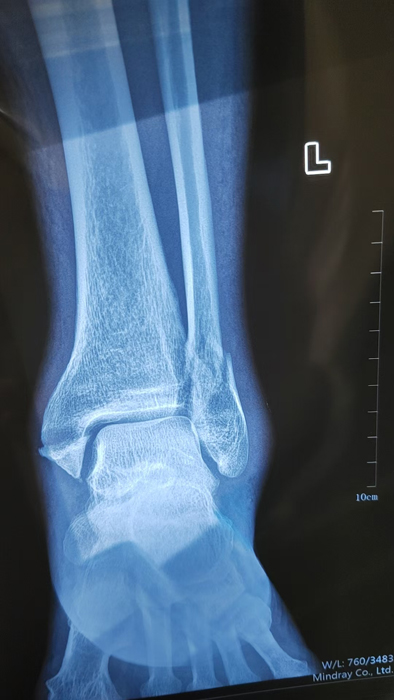

2月4日,何店镇中心卫生院接诊一名左踝关节外伤患者,经影像检查,确诊为左胫、腓骨下段骨折。外科医生姜稳迅速完成术前检查及病情评估,并与患者及家属深入沟通治疗方案。在患者强烈要求于本院进行手术的情况下,为最大限度保障手术质量与安全,该院特邀请医共体牵头单位——曾都区人民医院脊柱创伤外科专家团队前来指导。